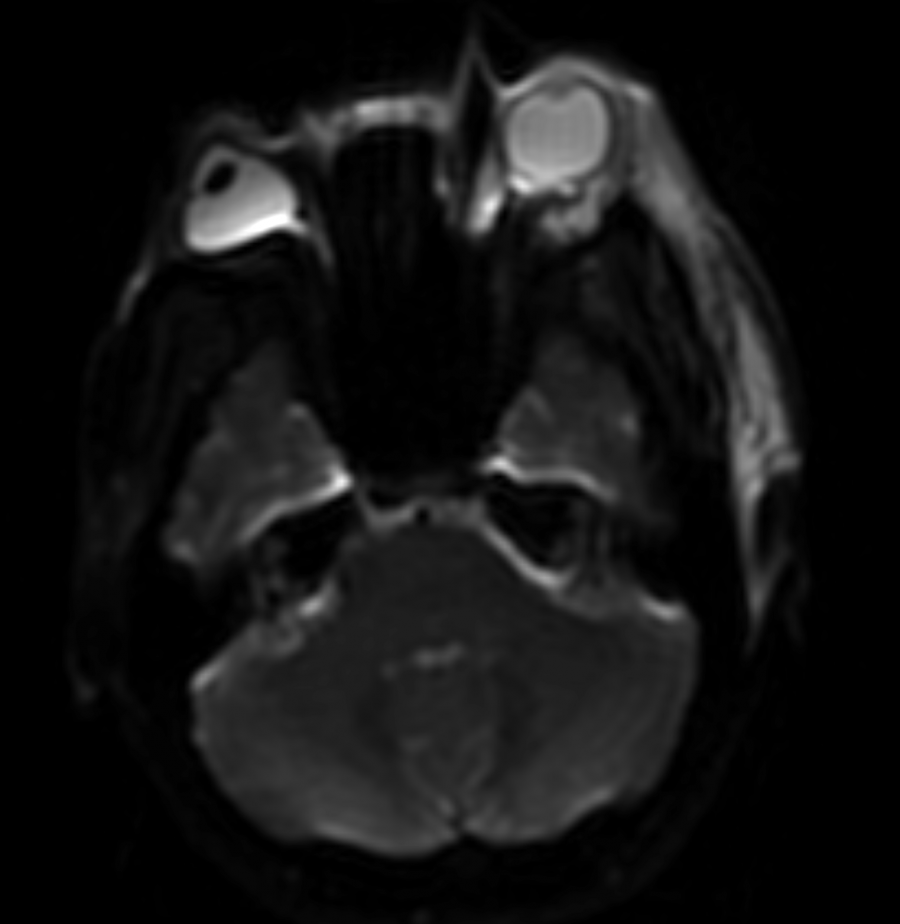

CT of the head and orbits should be obtained to rule out other etiologies, and it is classically notable for the presence of preseptal soft tissue swelling.

MRI with gadolinium may reveal engorgement of extraocular muscles and/or the lacrimal gland.[5] It may also demonstrate areas of intracerebral ischemia.[6][7] Examination of the macula will reveal retinal thickening with subretinal edema.[6]